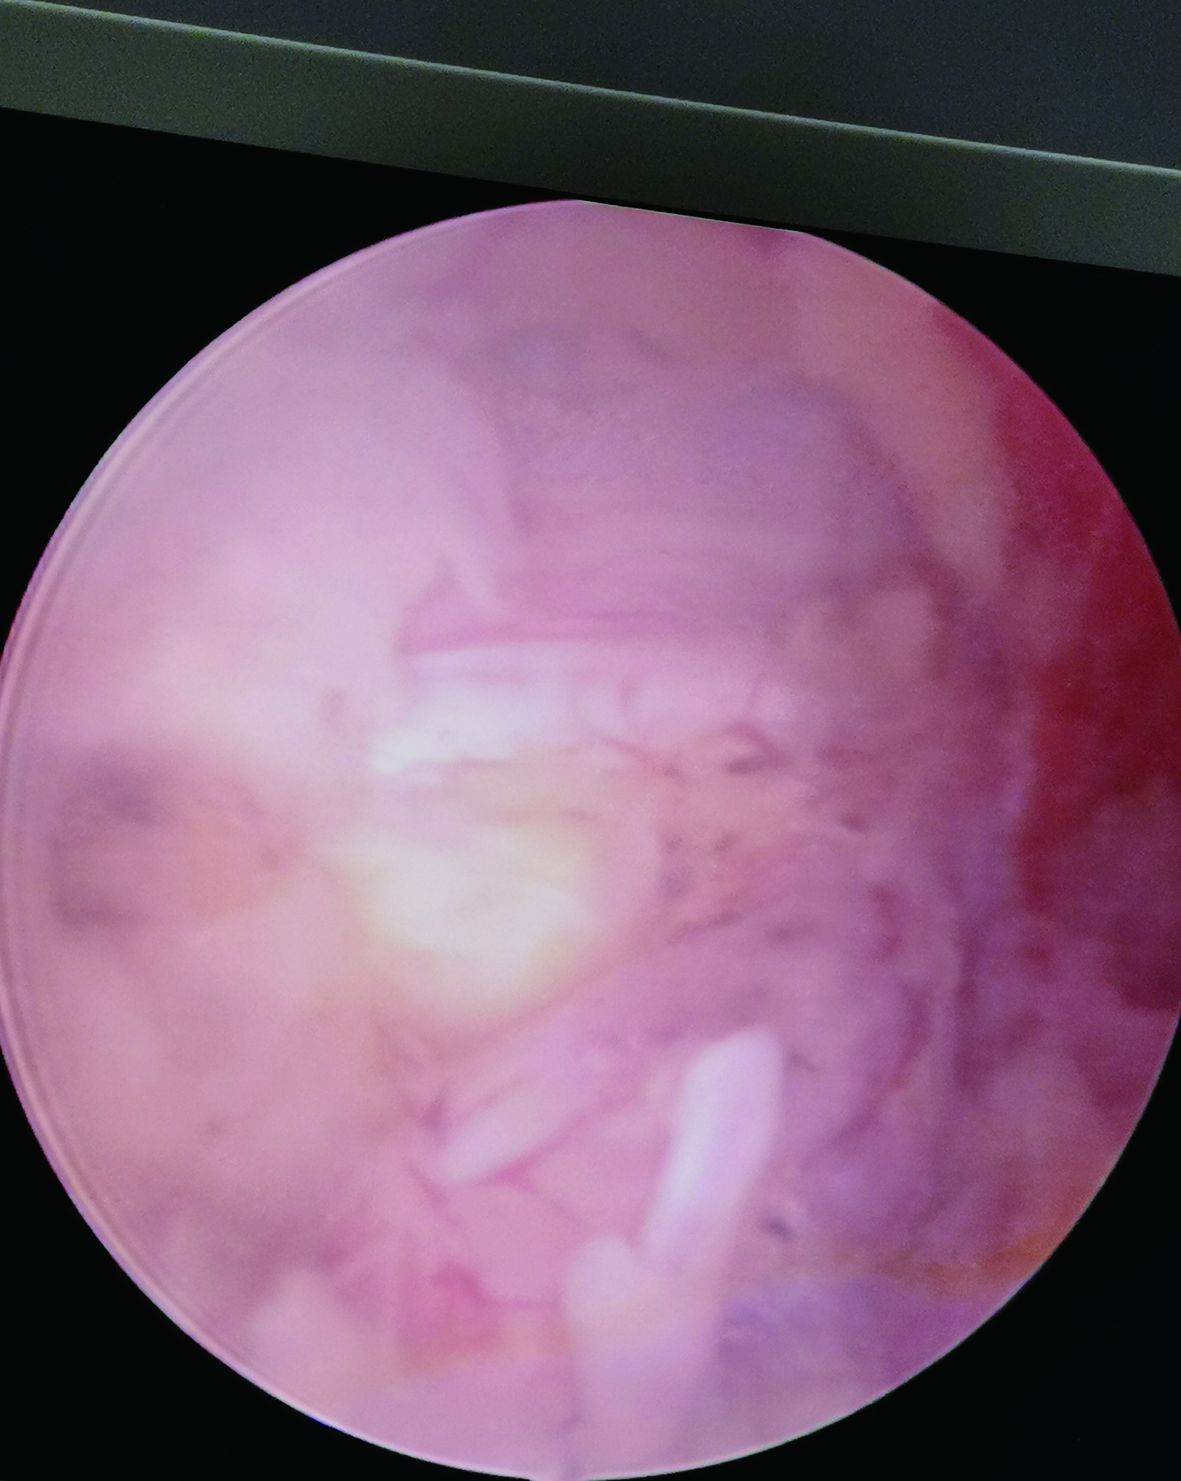

▲椎管減壓

▲取出髓核

經(jīng)過精密的術(shù)前準(zhǔn)備,術(shù)中使用UBE專用器械和等離子射頻手術(shù)系統(tǒng),視野清晰,操作靈活,椎板減壓,在保護神經(jīng)根和硬膜囊的前提下輕松摘除脫出的椎間盤髓核,與傳統(tǒng)手術(shù)相比,該手術(shù)方式兼具微創(chuàng)、安全、有效、并發(fā)癥少等顯著優(yōu)勢,病人背部只有兩個2cm的小切口。患者術(shù)后腰腿疼痛癥狀消失,術(shù)后第二天即可下床行走,手術(shù)效果顯著,得到了患者及家屬的高度認(rèn)可。